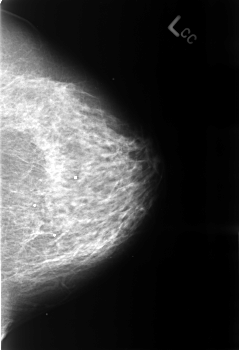

Volume: benign_without_callback_01 Case: B-3242-1

B_3242_1.LEFT_CC

LEFT_CC LINES 4544 PIXELS_PER_LINE 3104 BITS_PER_PIXEL 12 RESOLUTION 50 NON_OVERLAY